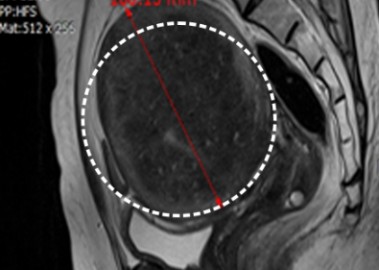

장막하근종 치료 사례